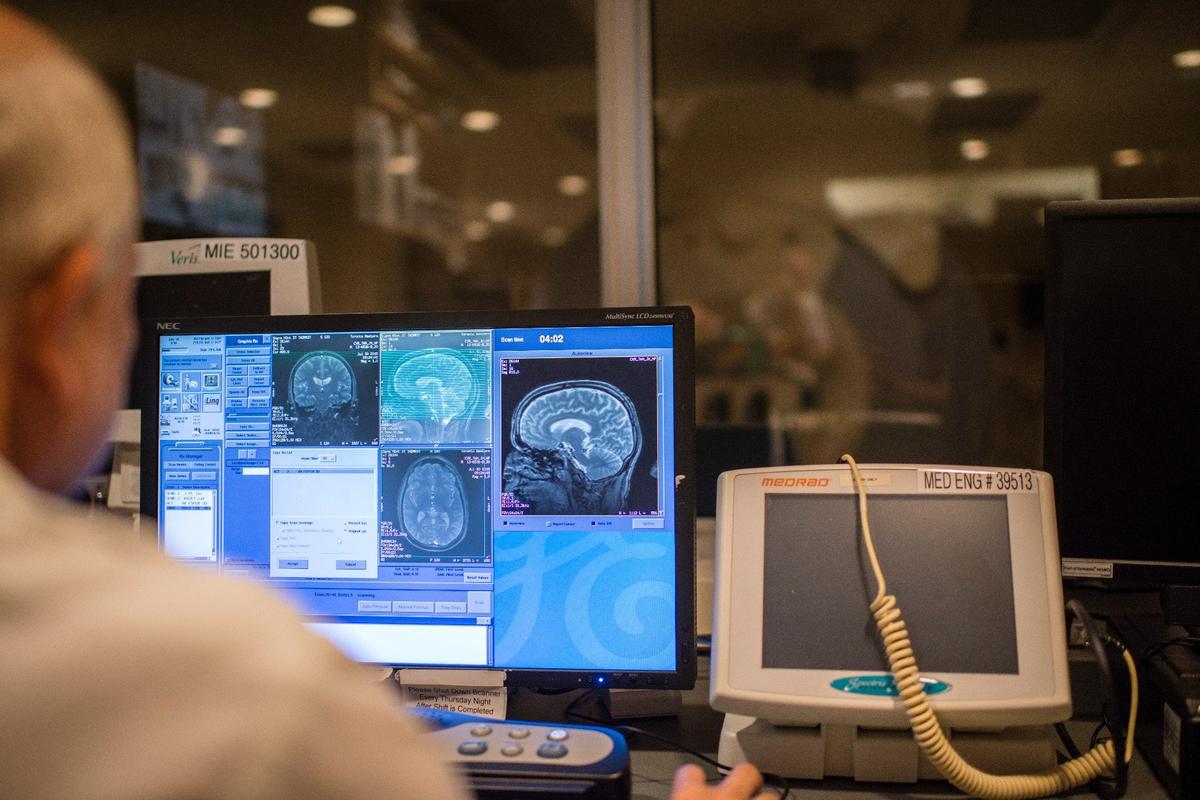

Возвращаясь к диагностике: как мы можем прижизненно поставить диагноз? Прижизненно это мы можем заподозрить при, во-первых, клинической оценке, когда мы констатируем при помощи ряда когнитивных тестов, что страдает оперативная память, и что нет каких-то других неврологических или нейропсихиатрических симптомов, которые противоречат диагнозу болезни Альцгеймера.

Дальше это подкрепляется данными нейровизуализации — в идеале МРТ, где мы можем видеть, что есть атрофия, то есть уменьшение в объеме преимущественно гиппокампов, если это классическая болезнь Альцгеймера, либо, например, уменьшение в объеме затылочных долей, затылочно-теменного стыка (при задней корковой атрофии).

Но этого опять же недостаточно, чтобы поставить диагноз, то есть на этом этапе мы можем только заподозрить синдром: например, легкие когнитивные расстройства, которые в России упорно переводятся с английского языка как «умеренные когнитивные расстройства», или деменцию. При легких когнитивных расстройствах имеющиеся нарушения не влияют на функциональную активность человека, на его повседневную жизнь. Если в рамках легких когнитивных расстройств мы видим, что страдает преимущественно домен оперативной памяти, то это подозрительно в отношении болезни Альцгеймера, но этого недостаточно для постановки диагноза.

Однако, по имеющимся на сегодняшний день данным, более специфичным в отношении диагностики болезни Альцгеймера является не измерение содержания бета-амилоида и тау-белка в цереброспинальной жидкости, а проведение позитронно-эмиссионной томографии (ПЭТ) с введением лигандов, связывающихся с патологическим бета-амилоидом. ПЭТ позволяет продемонстрировать физическое наличие бета-амилоида с нарушенной конформацией в головном мозге и то, что его отложения доминируют в области височных долей, в области гиппокампа.

ПЭТ на бета-амилоид является, к слову, способом выявления людей на самых ранних стадиях болезни Альцгеймера, когда еще нет, например, каких-то грубых или даже легких когнитивных расстройств, но при этом уже имеются отложения агрегатов бета-амилоида. Если провести всем условно здоровым людям ПЭТ на бета-амилоид, то мы можем выявить определенную когорту людей с наличием этого бета-амилоида в головном мозге, но пока без каких-либо симптомов, которые могут проявить себя через 10–30 лет. Это связано с тем, что агрегация белков с патологической конформацией при нейродегенеративных расстройствах начинается значительно раньше того, как появляются внешние симптомы болезни. То есть имеет место так называемый латентный период от формирования этих агрегатов до проявления симптомов, и он может быть довольно длительным, и в зависимости от болезни может варьировать: при болезни Альцгеймера латентный период может составлять где-то 20 лет, до 30 лет даже, при болезни Паркинсона — примерно в таком же диапазоне, 20 лет. Есть еще одно нейродегенеративное заболевание, которое иногда называют инфекционным, но это не очень корректно: это прионные болезни, которые также являются нейродегенеративными, также связаны с агрегацией прионного белка. Такой белок также есть в норме, но при этих заболеваниях он меняет свою конформацию и образует агрегаты. У них тоже очень длительный латентный период.